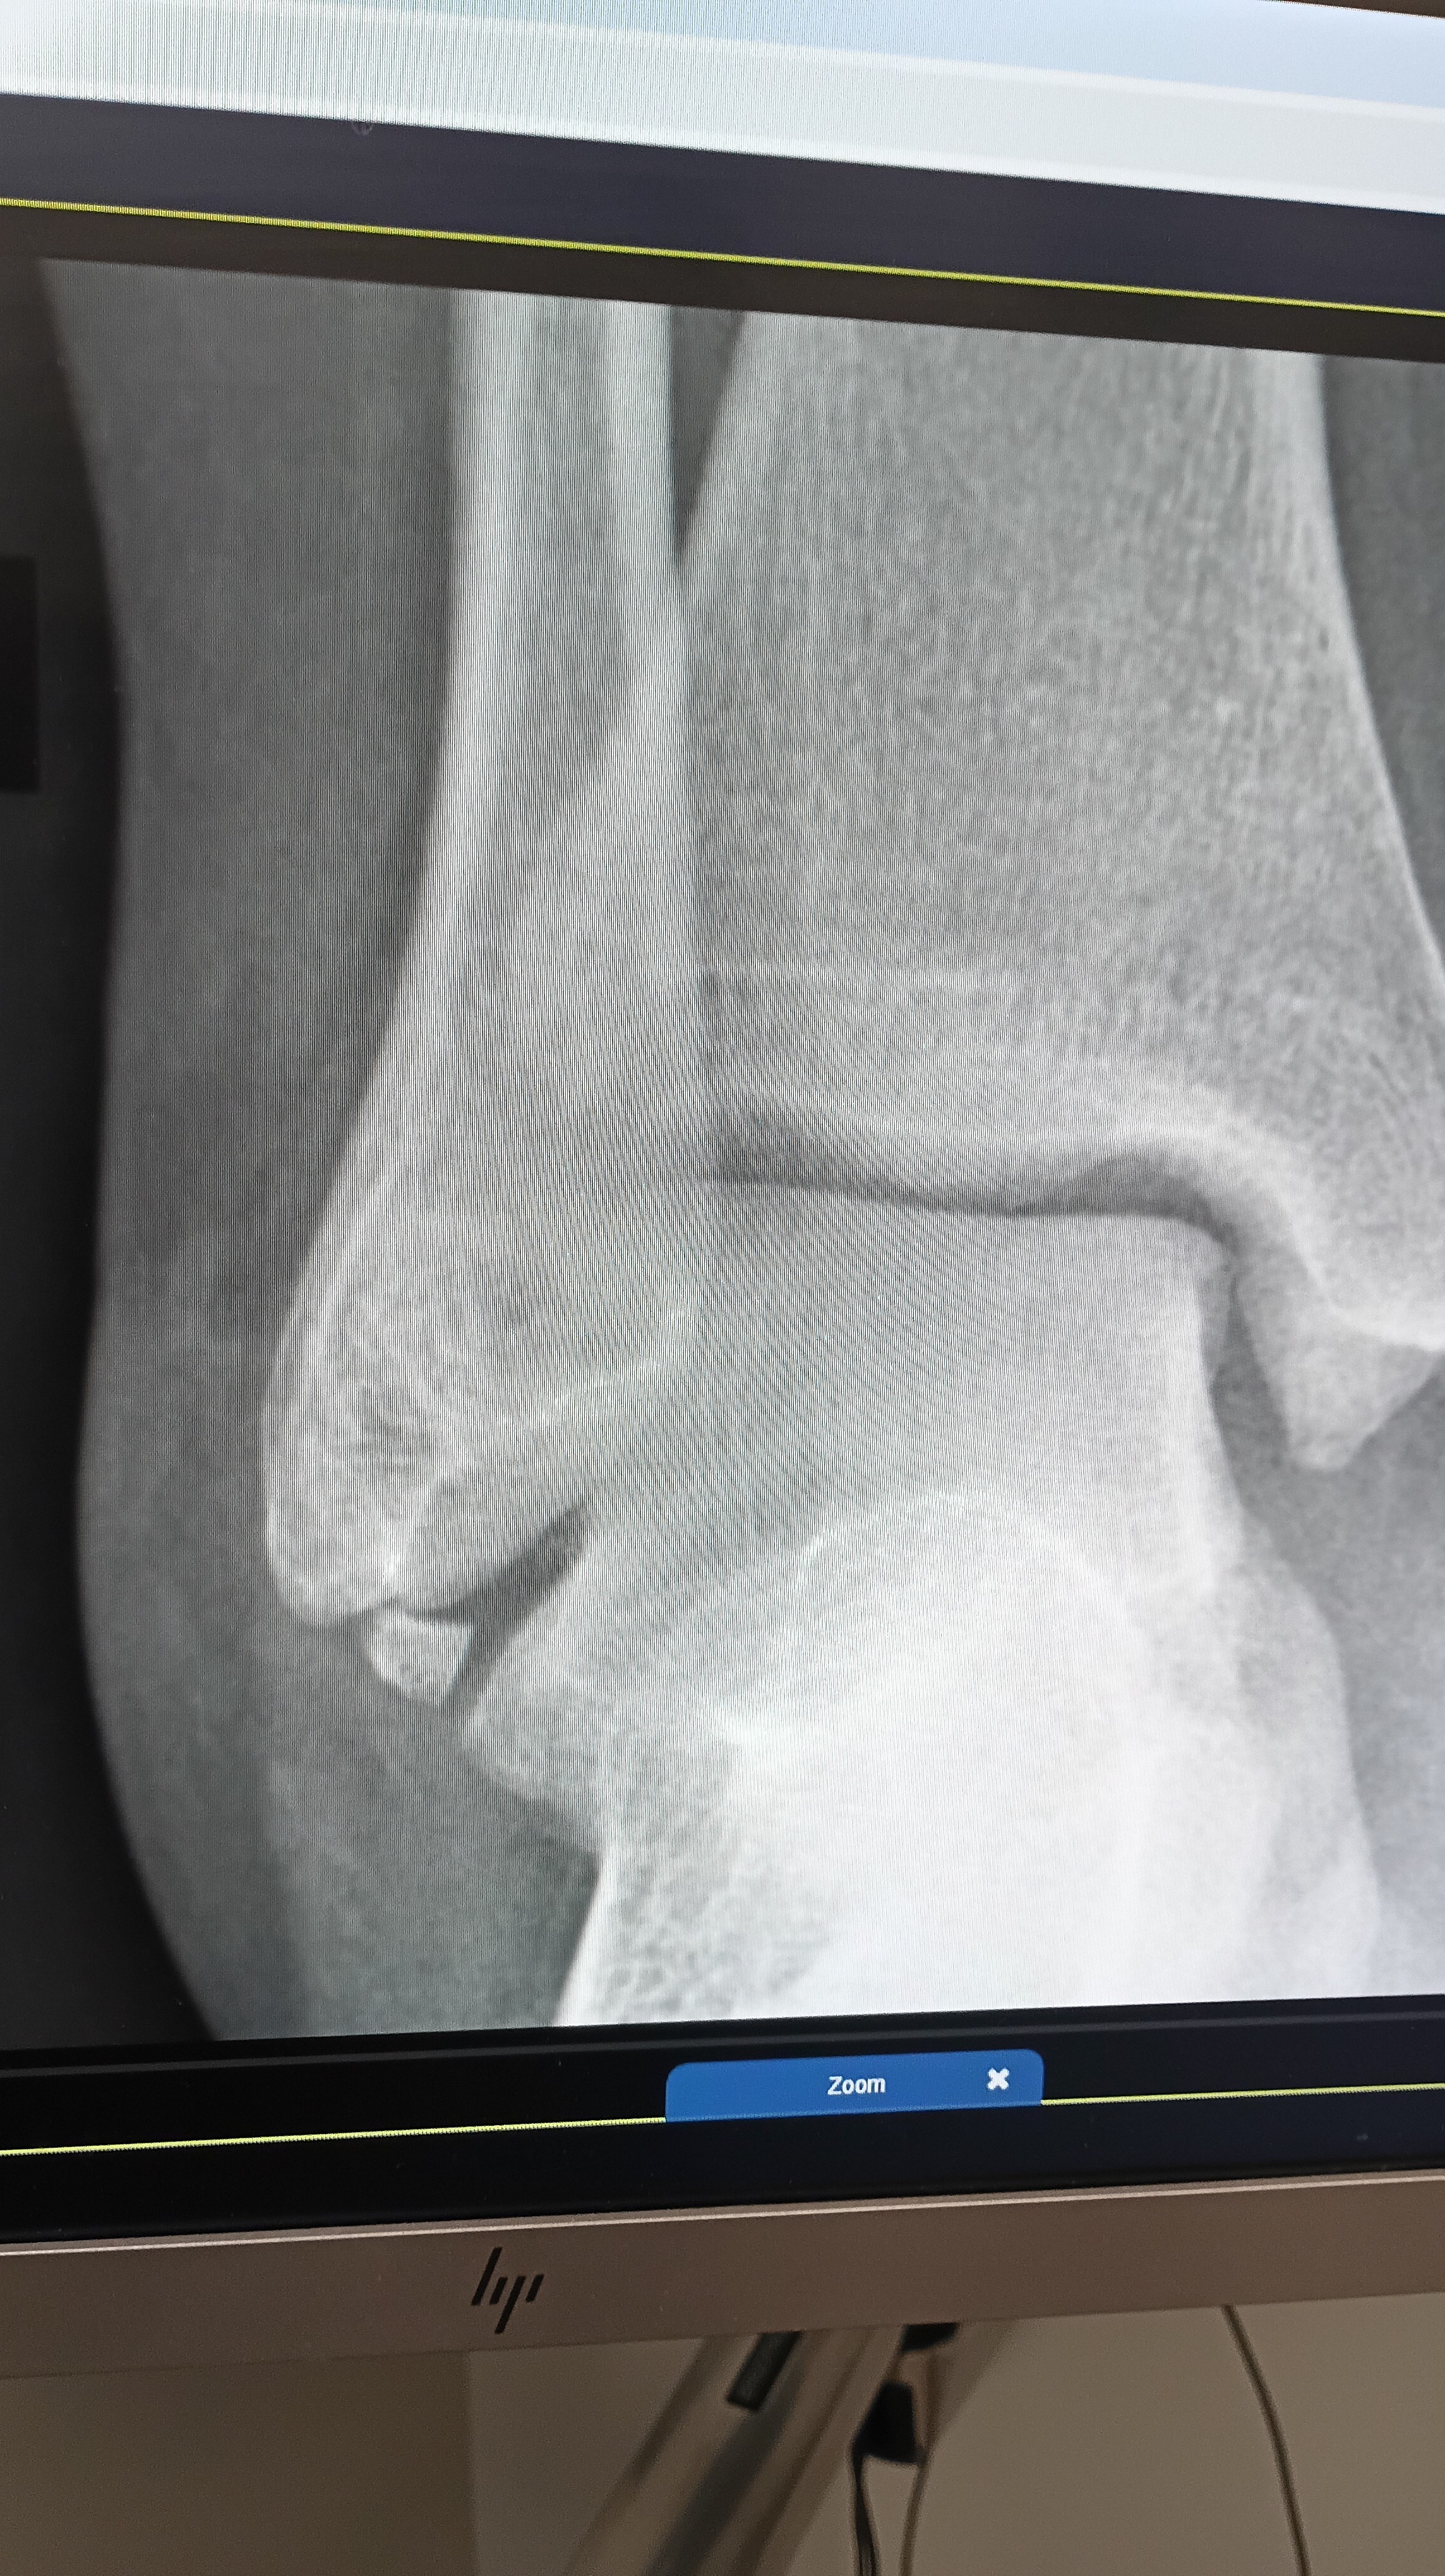

Hi, my name is Tanya Rowland, and I broke my ankle in January of this year. I was able to work at first. I recently had an MRI, and it showed I have two different breaks and a torn ligament that is holding on by fibers. I need to have surgery to reconstruct and reconnect it back to the bone. I also need to have the piece of a bone that broke off taken out.